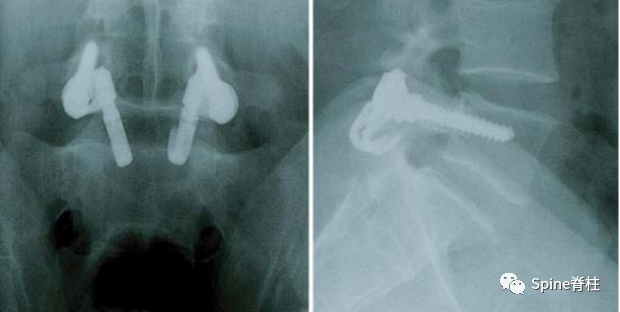

随着内固定的发展,既往峡部单纯修复植骨因融合率低、卧床时间长,现已很少应用。而植骨修复并节段固定有多种方法,包括Scott接线法、Buck螺钉法、Louis的蝶形板、钉钩技术(椎弓根螺钉和钩-棒系统)、U形棒等。从临床角度看,钉钩技术可以用刚性植入物固定断裂的峡部,并沿椎板方向施加作用力,有效稳定峡部,这对于达到更好的骨性愈合是至关重要的。理论上,此种方法更符合生物力学,对邻近节段影响小,但应把握好适应症,建议单纯腰椎峡部裂伴或不伴轻度滑脱患者可行植骨修复并节段固定。

1. 椎弓根螺钉-钉钩系统

PMID: 9199377

PMID: 15699811

PMID: 17520298